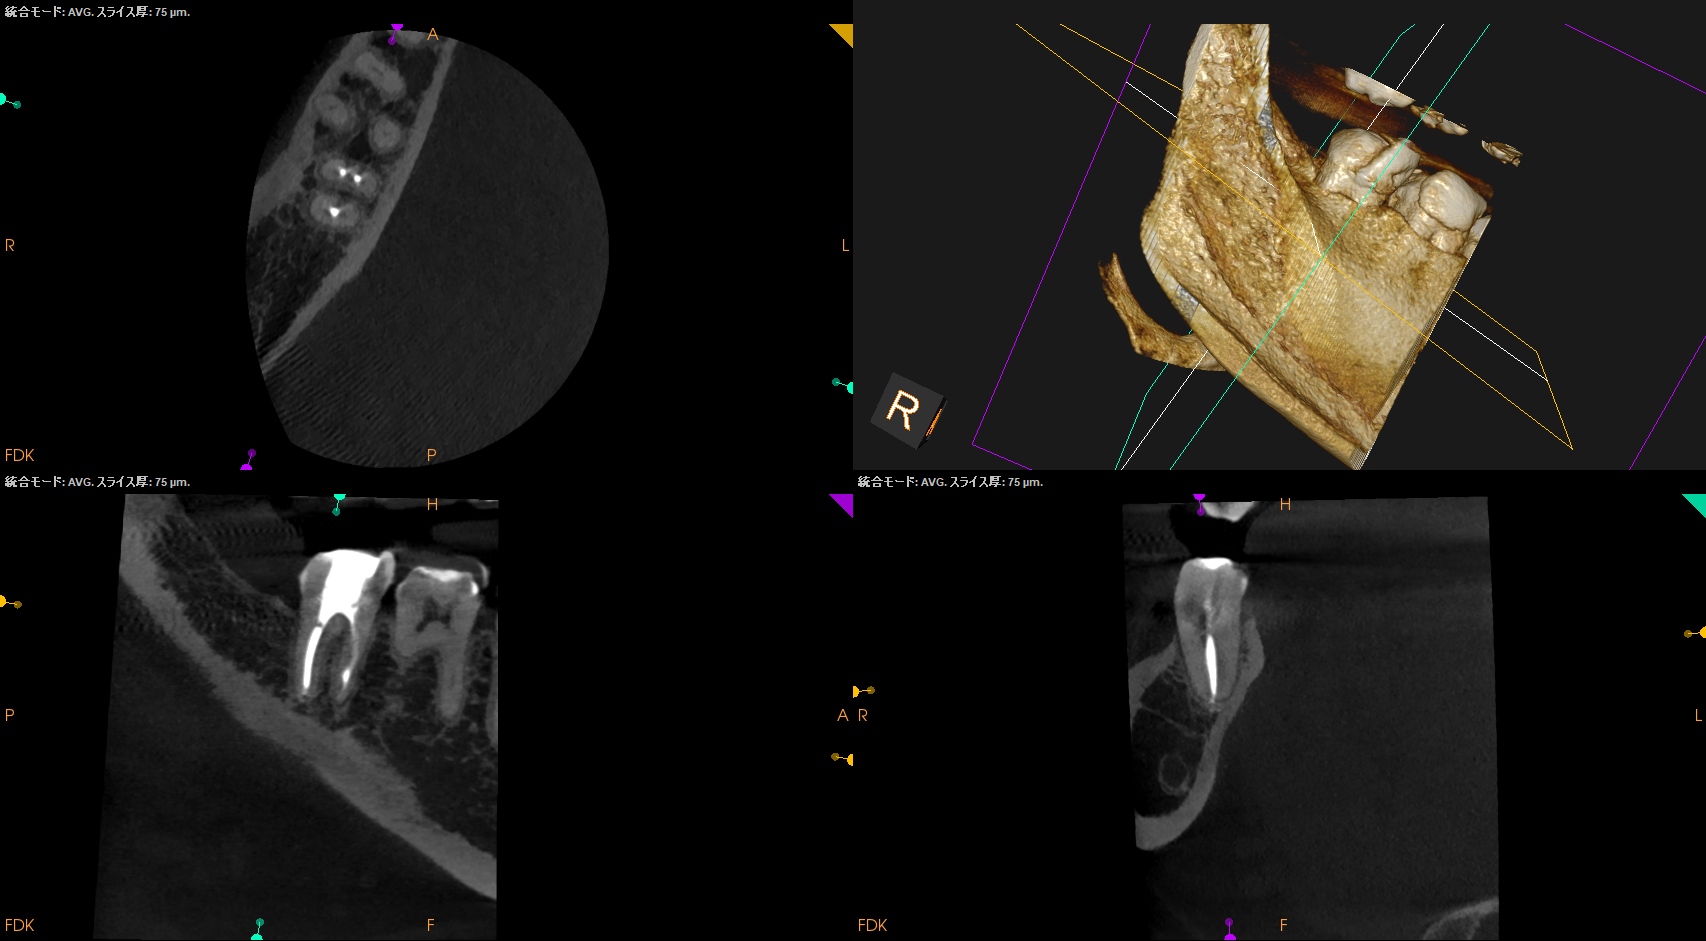

以下のように根管形成した。

Dは#60.02で形成しても出血がペーパーポイントに見られたためにProTaper Gold F5まで形成した。

ML,MBは合流していることが多いと言う解剖学的情報をもとに以下のように合流部分をチェックした。

問題はないだろう。